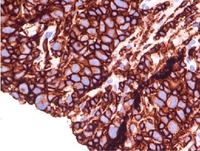

GZL CD-20

There is some variable positivity for CD20 staining in the large malignant cells.